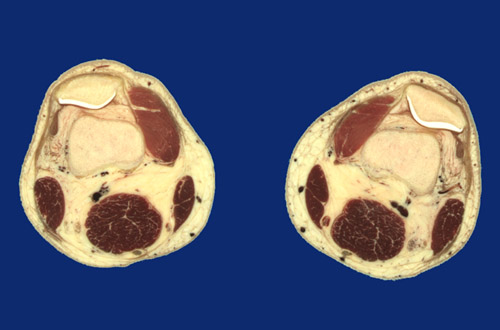

Identify the following regions in the image above: Great saphenous vein - Popliteal vessels - Sciatic nerve - Vastus medialis - Sartorius - Gracilis - Semitendinosus tendon - Semimembranosus - Biceps femoris - Synovial space - Articular cartilage - Patella - Femur